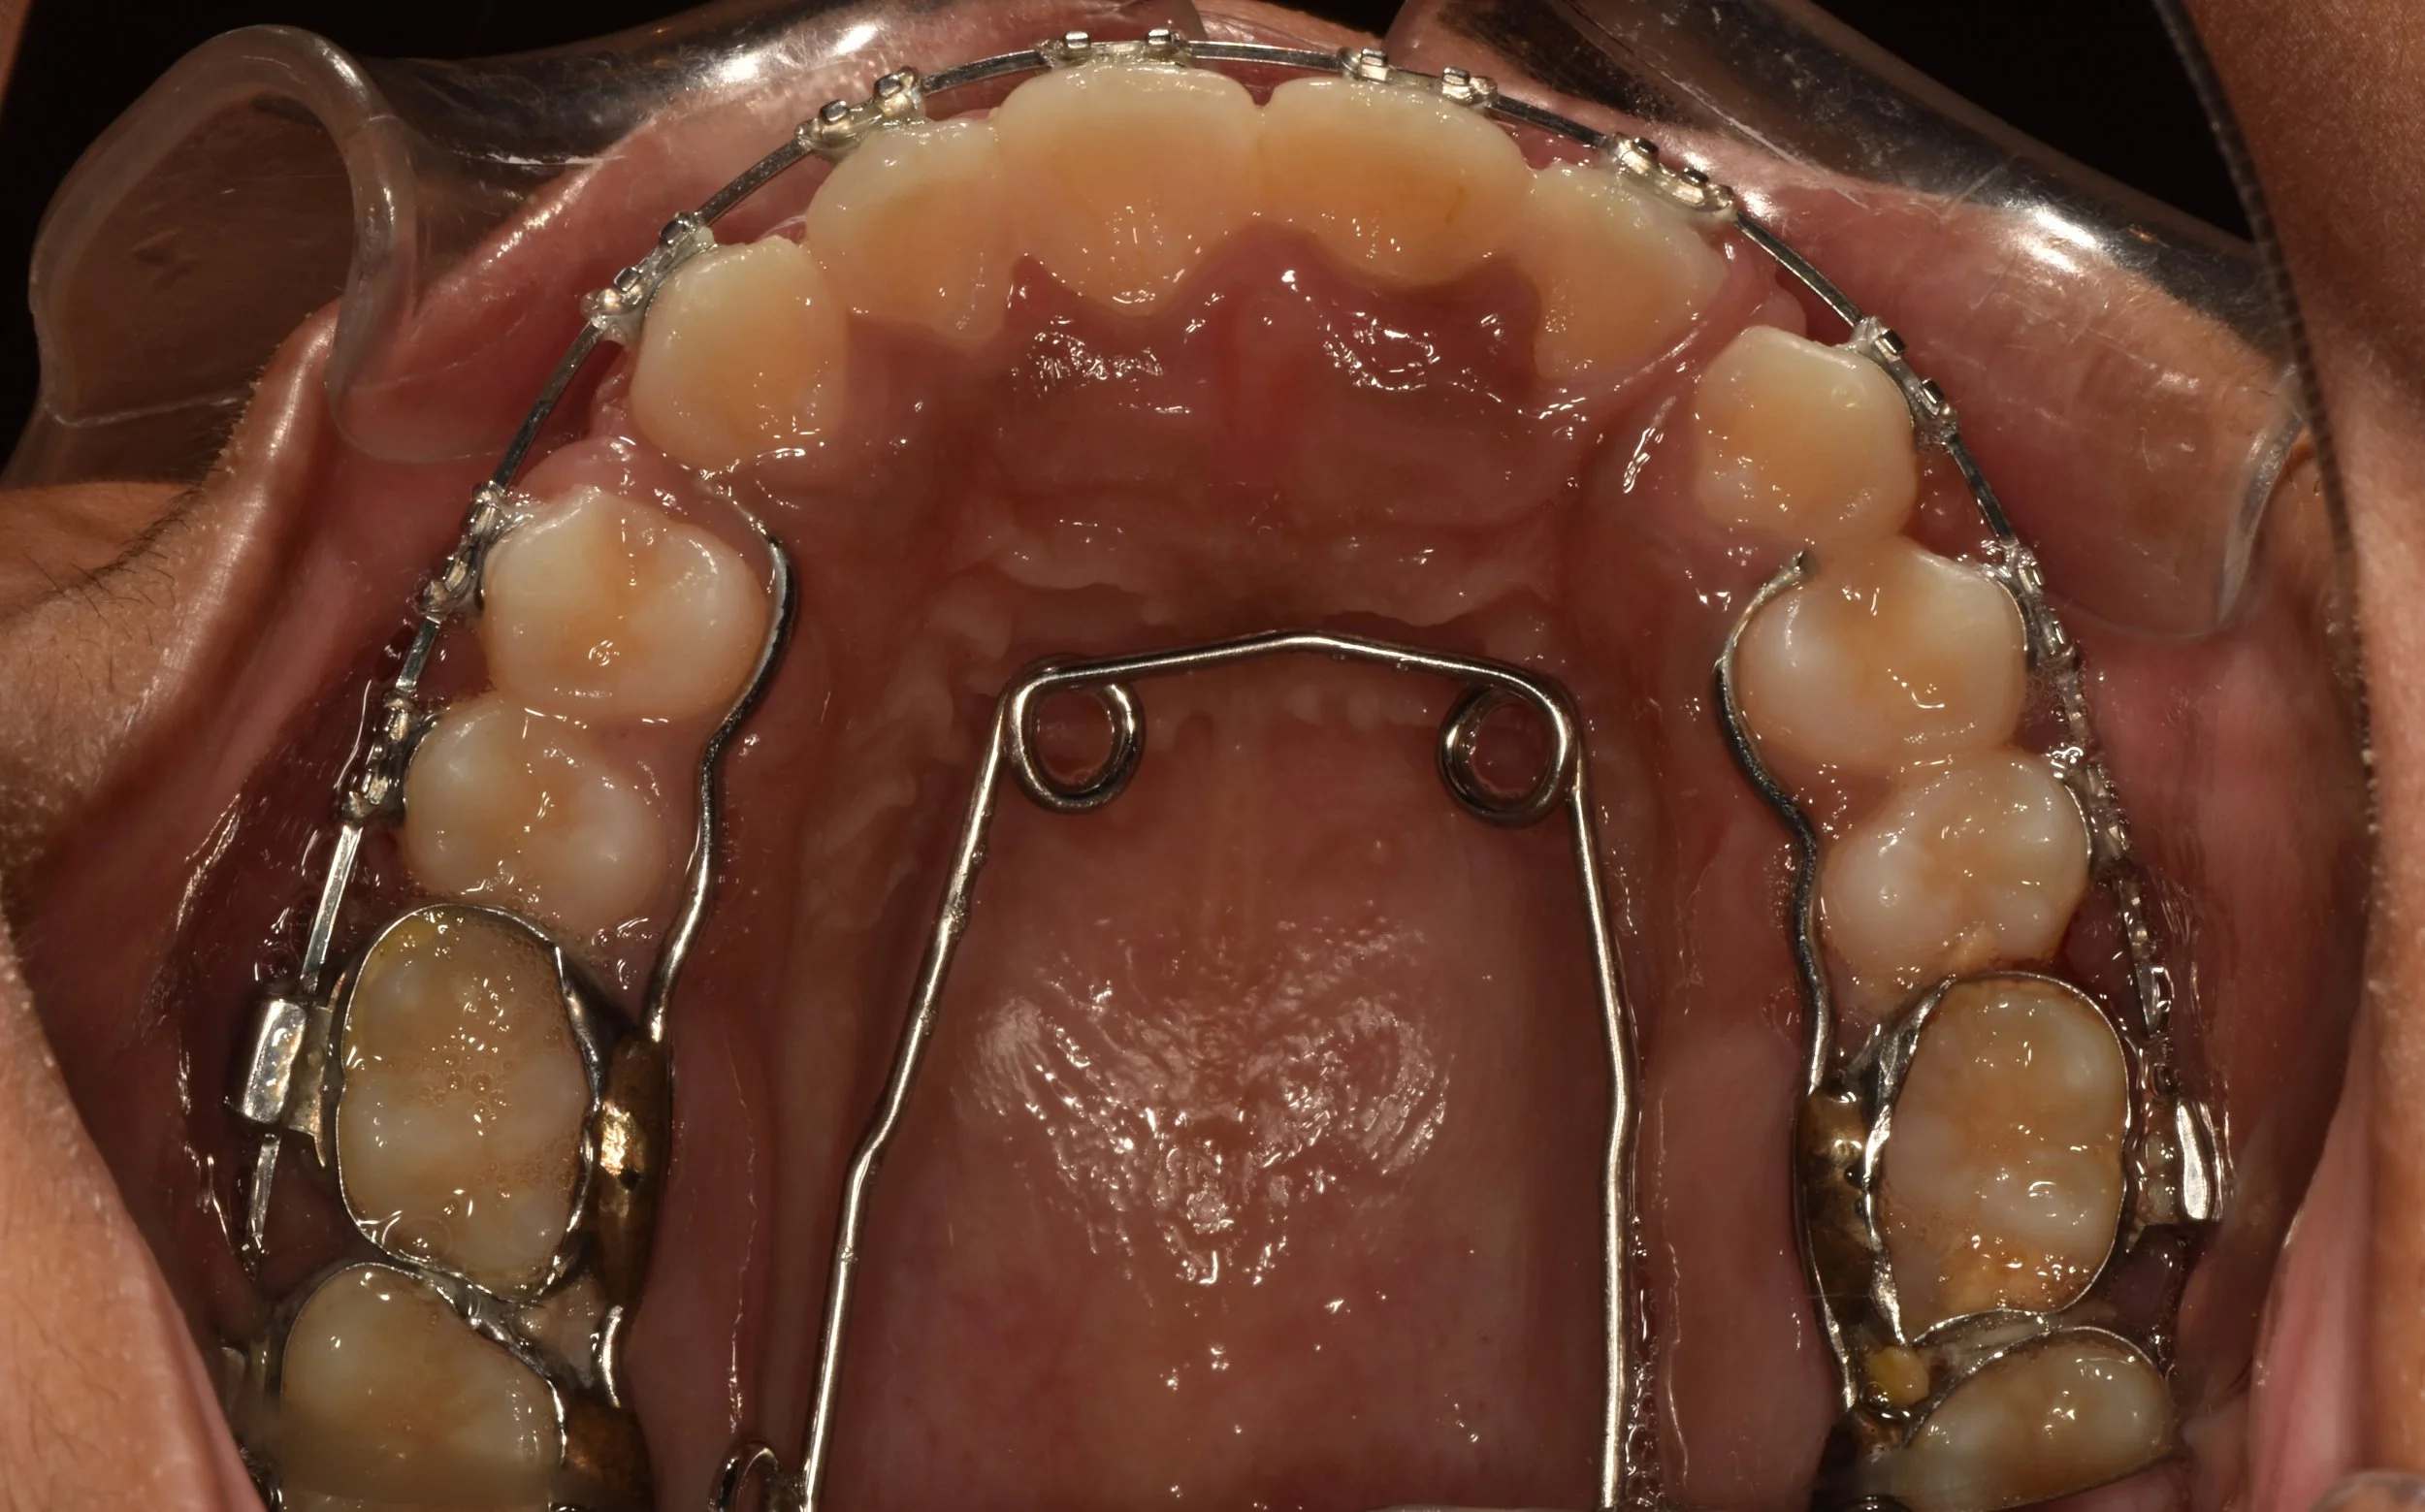

Orthodontic disimpaction of locked tooth